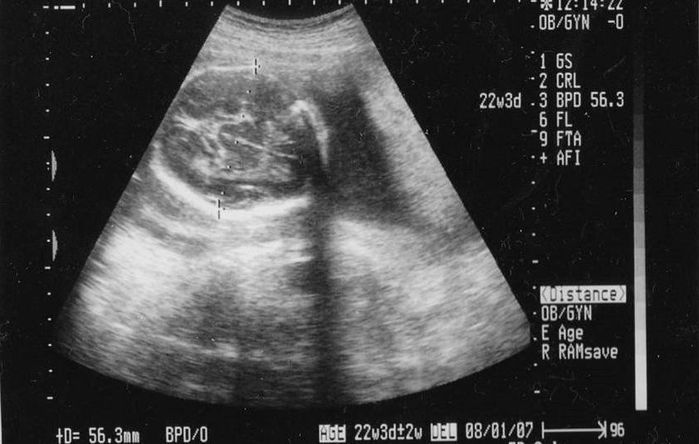

22週目のエコー写真

脳が半分に分かれているかのチェック。